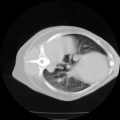

CT ledvin